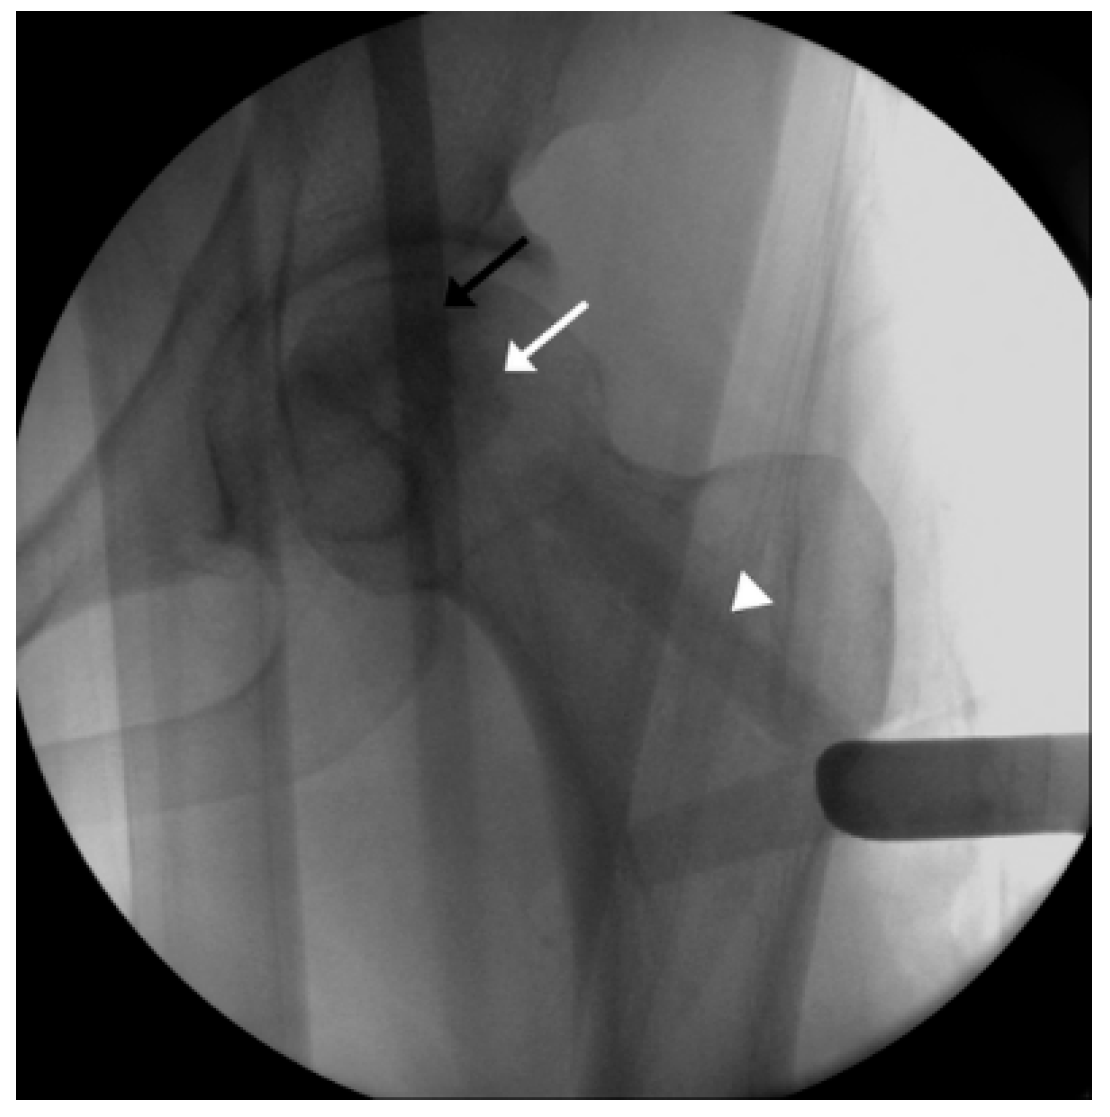

2.5. Procedure